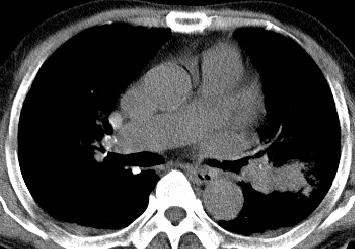

以下是引用光影相伴在2008-4-20 14:39:00的发言:[br]支持:1)左侧中央型肺癌伴左肺上叶阻塞性肺炎。、[br] 2)双侧少量胸腔积液。

以下是引用xianxianzhongyi在2008-4-20 14:44:00的发言:[br]本人愚见:次病例短短两月的时间,呈现如此大面积实变,病变增长过于迅速,此其一。其二,病变在动脉早期既有明显强化。其三,左上叶后段及下叶背段多叶受累。其四,肺门及纵隔内未见明显肿大的淋巴结。估计层面较厚段支气管显示不清。 诊断:炎性实变可能性大。